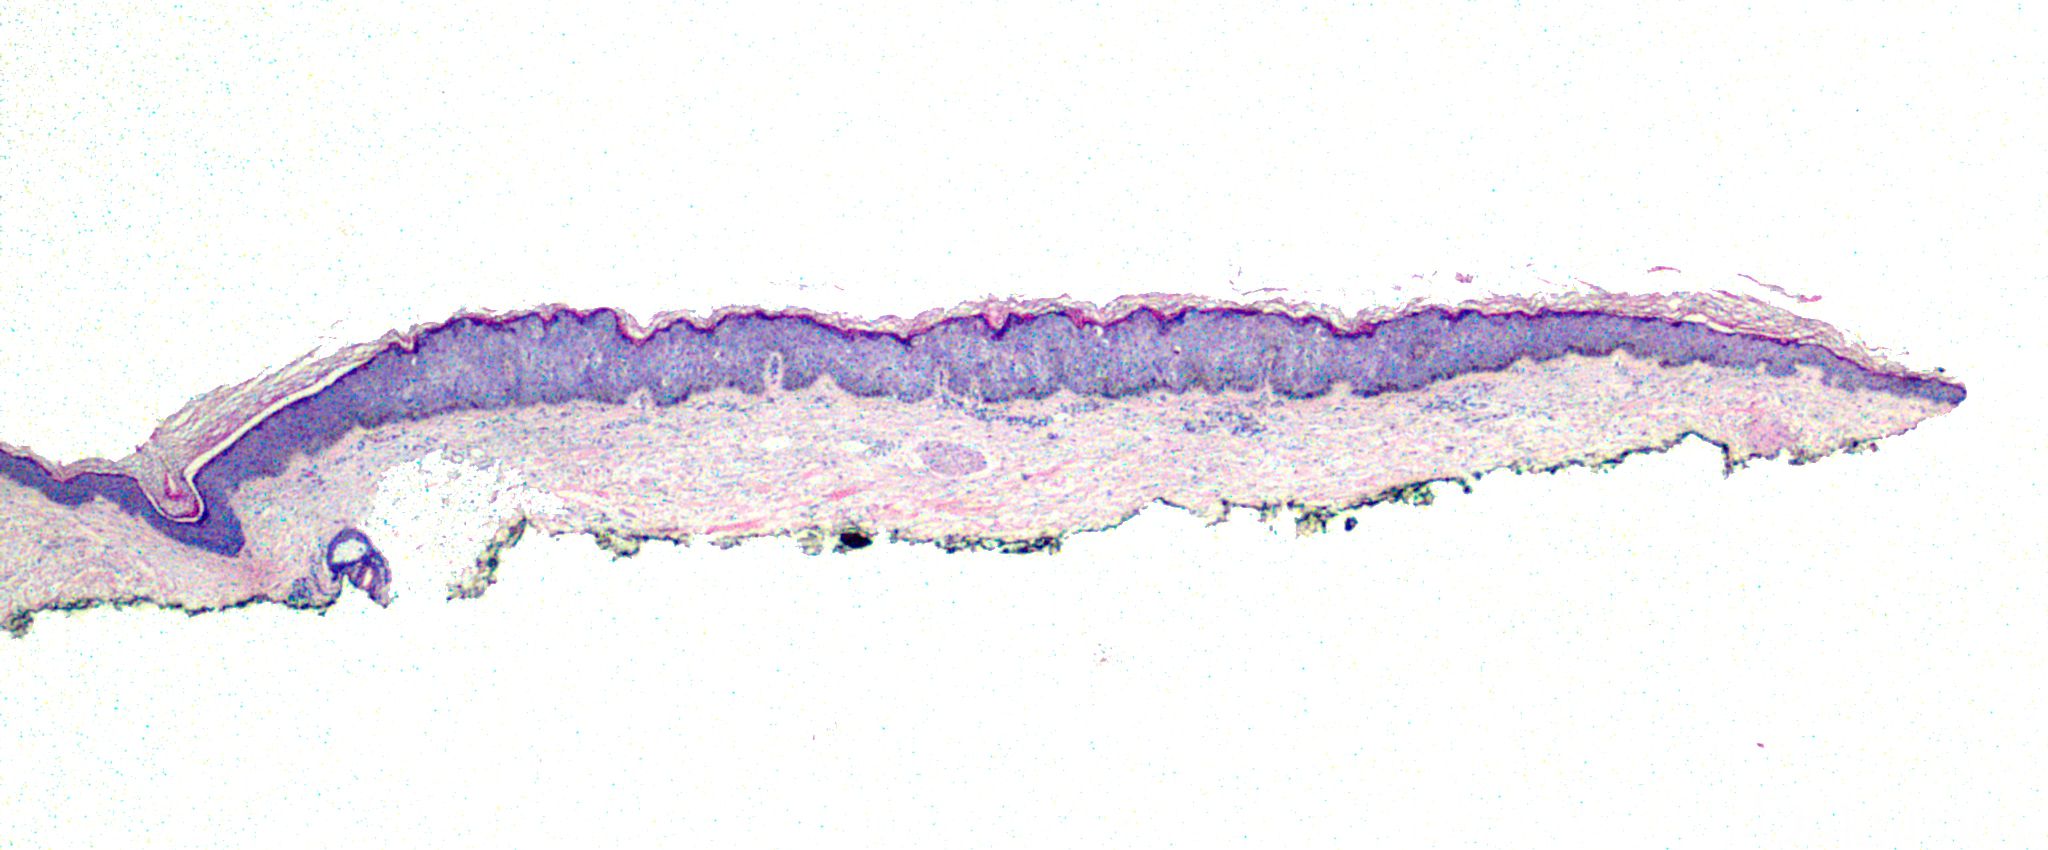

好发于中老年病人,多见于头部和四肢日光暴露部位,表现为边界清楚、微隆起,略有鳞屑的丘疹或棕褐色斑块

表皮萎缩或略微增厚,轻度角化过度,局部区域可见增大的角质形成细胞聚集;

大角质形成细胞可见于表皮各层,体积约是周围正常细胞的两倍,无核异型性,无分裂像;

基底细胞可色素增多,上皮脚往往呈球茎状增大,核分裂仅见于基底层。